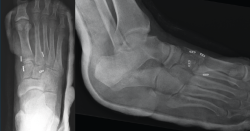

Figura 2. Caso 1. Resultados radiográficos posquirúrgicos.

Se realiza la intervención quirúrgica a las 8 semanas con reducción abierta mediante abordaje dorsomedial confirmando la inestabilidad articular y realizando una estabilización con sutura intraósea con botón de C1-M2. Se comprueba que aún persistía cierta inestabilidad en el plano frontal, por lo que se decide poner otro dispositivo de C2 a M1. Se inmoviliza con una férula suropédica y se indica descarga (Figura 2).

Figura 3. Caso 2. A: radiografía preoperatoria anteroposterior con diástasis en la articulación de Lisfranc; B: radiografía oblicua preoperatoria; C: corte de tomografía computarizada oblicuo.

Se trata de una mujer de 26 años atendida en urgencias tras un traumatismo con torsión del pie. Se realiza radiografía y TAC, objetivando diástasis de 9 mm sin lesión ósea (Figura 3) y diagnosticando, por tanto, lesión sutil de Lisfranc.